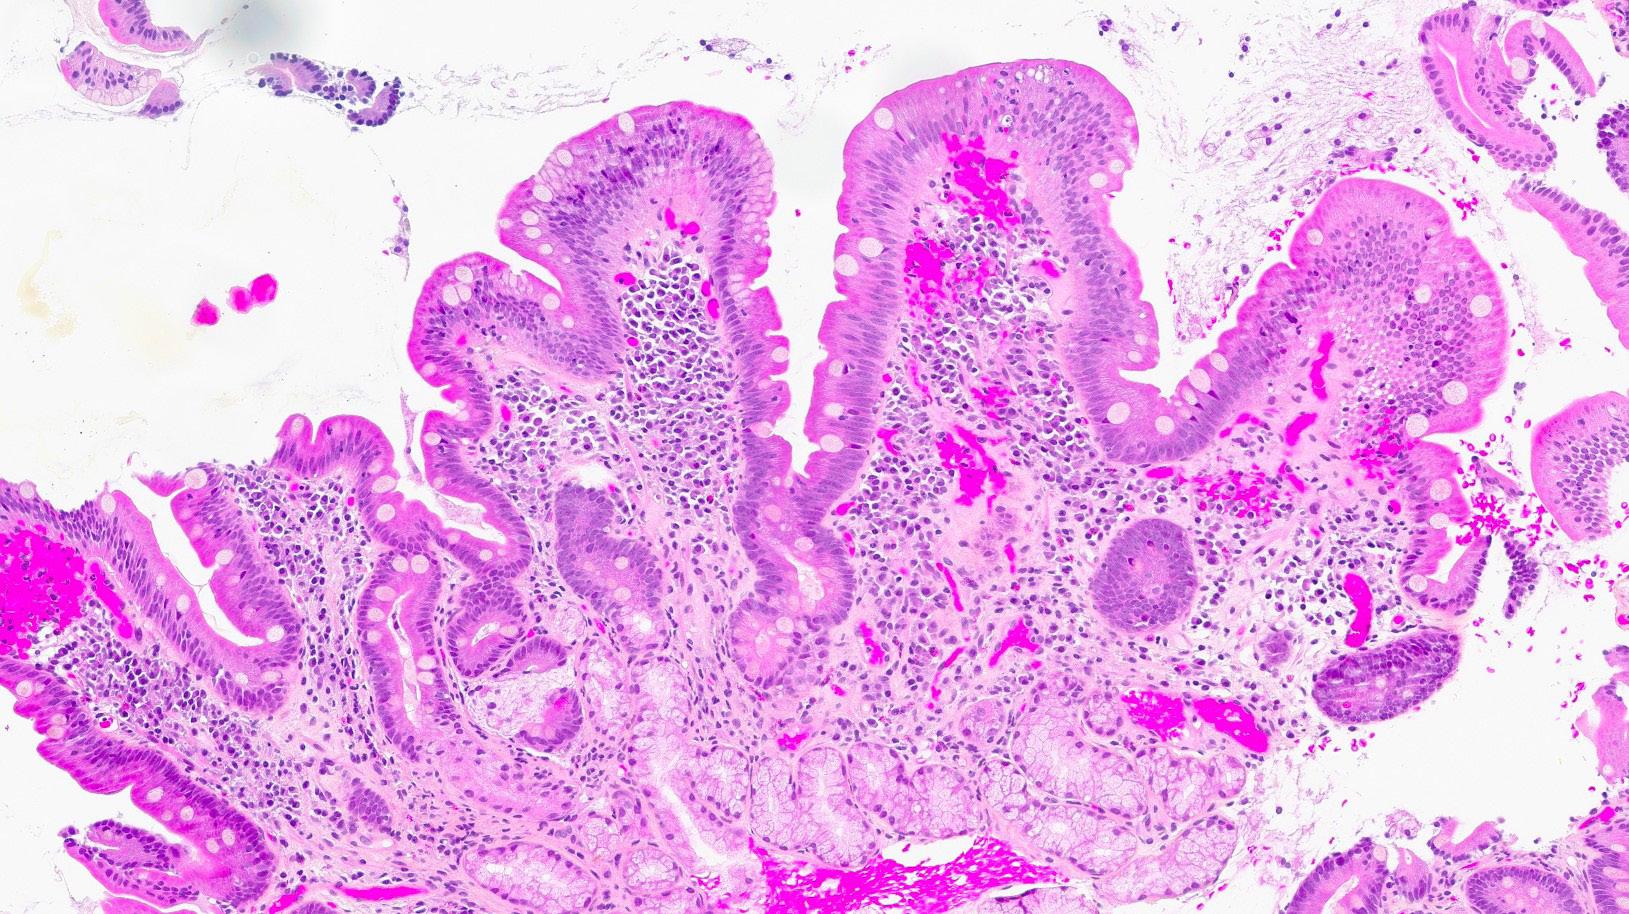

To måneder senere hadde pasienten lagt på seg 5 kg, og hadde mer normalisert avføring. Magesmertene var borte, og håret hadde begynt å komme tilbake. Kontollbiopsi fra duodenum et år senere viste normalisering av slimhinnen med kun mindre områder med ombygget tottearkitektur og gastrisk metaplasi (bilde 3). Vekten var stabil, og hun hadde ingen abdominale plager.

Bilde 3: (HES, 120x) Etter seponering. Biopsi fra duodenum (artefaktpreget med «hakk») med tilnærmet normale funn. Et mindre fokus gastrisk metaplasi i overflateepitelet (nede til høyre).